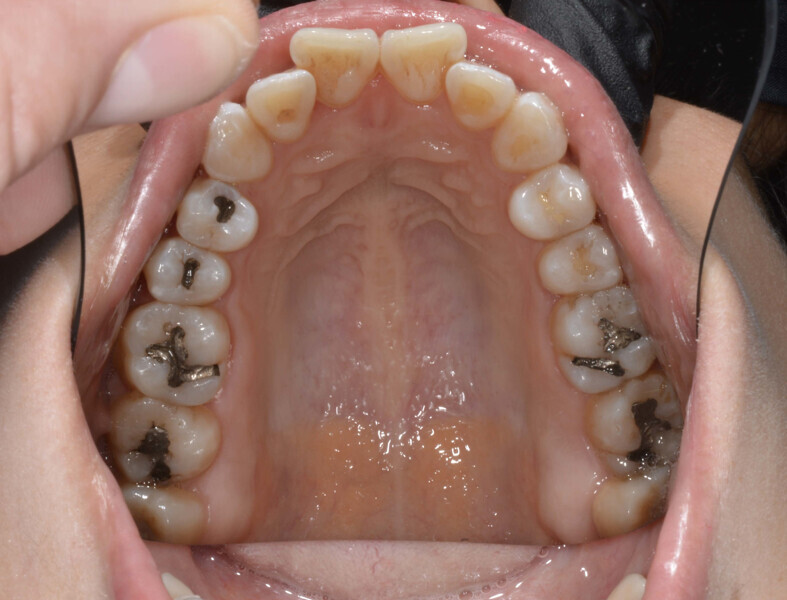

A 35-year-old female patient presented with crowding, muscle and joint pain, and headaches upon awakening. Examination found a skeletal Class I with crowding and bimaxillary protrusion. Facial examination showed a convex profile with protruded lips and a square face shape, intensified on smiling (Figs. 1–4). She reported bruxism, and bilateral masseteric hypertrophy was observed, but there was no alteration of the temporomandibular joints.

Before the aligner treatment began, the maxillary and mandibular second premolars were extracted to create space. With orthodontic treatment, distalisation of the anterior teeth was achieved by employing maximum mandibular anchorage and moderate maxillary anchorage (Figs. 5–7). At the end of the treatment, a stable bilateral Class I occlusion had been achieved, as well as normal inclination and retrusion of the anterior teeth, consequently improving the profile (Figs. 8–10).